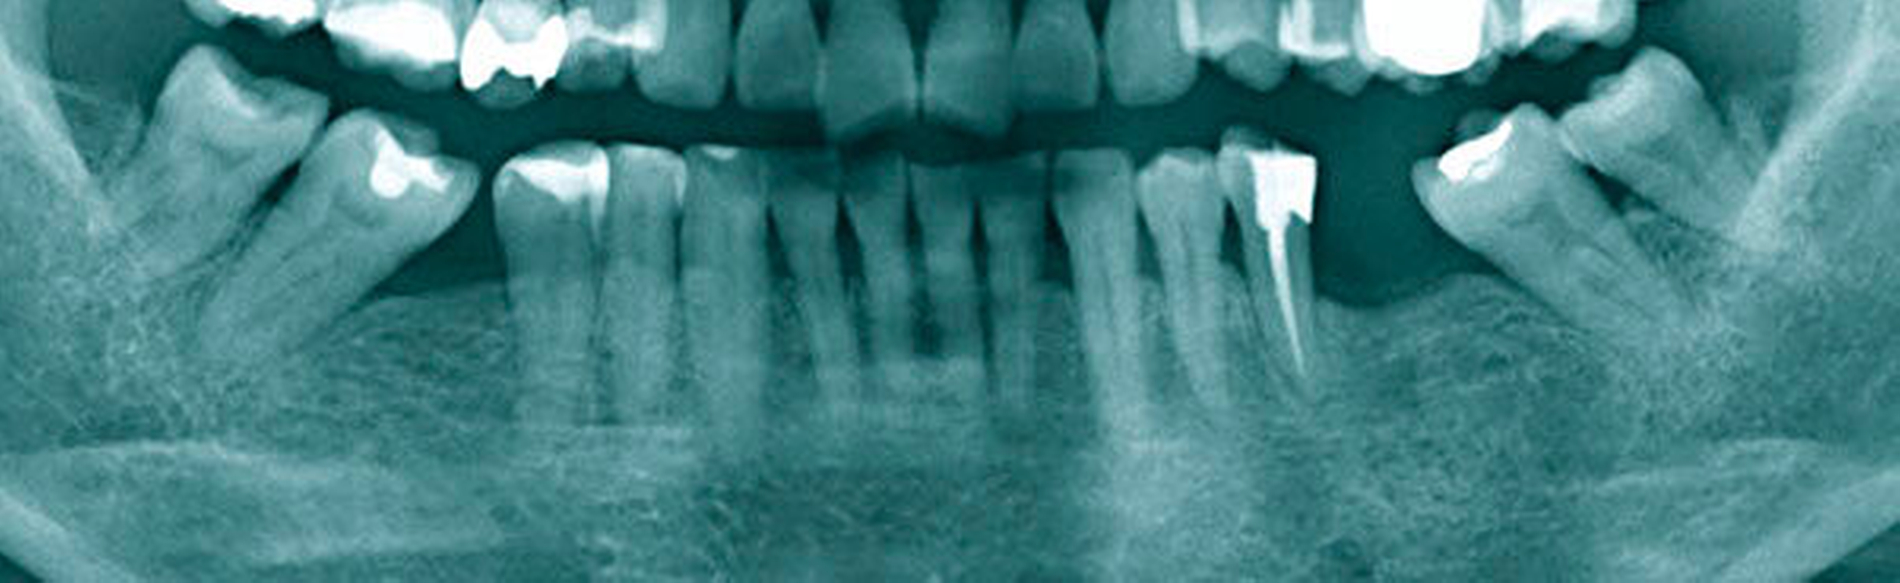

Abbildung 4: Überwachtes Monitoring (Belassen und Beobachten) von Zahnlücken

In der Zahnmedizin ist ein Dogma weit verbreitet: „Jede Lücke muss rasch geschlossen werden.“ Tatsächlich gibt es jedoch viele Situationen, in denen es ohne relevante funktionelle und ästhetische Einbußen vertretbar erscheint, eine Lücke zu belassen und regelmäßig zu beobachten (Monitoring). Derzeit erfolgt die Entscheidung „Lücke belassen versus Lücke schließen“ oftmals subjektiv. Sie ist zuweilen weniger von den Patientenvariablen abhängig als von den Schwerpunkten der betreuenden Zahnärzte (Abbildung 4) [Listl et al., 2016]. Ein fachlich fundiertes Vorgehen, das eine Entscheidung unter einer Nutzen-Risiko-Abwägung trifft und ein Monitoring in die Überlegungen einbezieht, kann ebenfalls in die Kategorie der frugalen Interventionen eingeordnet werden. Gleiches gilt für ein Vorgehen im Sinne des Prinzips der verkürzten Zahnreihe, das inzwischen wissenschaftlich gut evaluiert ist [Walter, 2016] und zu dessen Realisierung auch konservierende Maßnahmen beitragen können (Abbildung 5).

Falls ein Lückenschluss nach Gegenüberstellung der Vor- und Nachteile als angemessen angesehen wird, stellt sich die Frage, mit welchen Hilfsmitteln dies erfolgen soll. Derzeit stehen Implantate und klassische Brückenversorgungen im Vordergrund. Es gibt aber auch etliche nicht- oder minimal-invasive Alternativen, die zum Beispiel bei Einzelzahnlücken in Erwägung gezogen werden können. Dazu zählen unter anderem direkte Verfahren wie Zahnverbreiterungen oder -anhänger (Abbildungen 6 und 7) [Staehle, 2009 und 2012; Staehle et al., 2015]. Zurzeit kommen derartige Maßnahmen nur in Einzelfällen in Betracht, es bedarf noch weiterer Evaluationen, um ihr Indikationsspektrum genauer abgrenzen zu können. Es zeichnet sich aber jetzt schon ab, dass sie ein gewisses Potenzial als frugale Interventionen besitzen. Auch wenn momentan vielfach Implantate favorisiert werden, erscheint es dennoch sinnvoll, wenn die Zahnärzteschaft auch diverse Implantat-Alternativen vorhalten kann. Ungeklärte Probleme periimplantärer Entzündungen [Chrcanovic et al., 2016] und die zu erwartende Diskussion über Beziehungen zwischen periimplantären Entzündungen und der Allgemeingesundheit lassen es als sinnvoll erscheinen, solchen Fragen intensiver als bisher nachzugehen. Bislang wird zwar nur über Einflüsse der Allgemeingesundheit auf den Erfolg beziehungsweise Misserfolg von Implantaten diskutiert. Es ist aber nicht auszuschließen, dass man künftig die Fragestellung in umgekehrter Richtung dahingehend erweitert, inwieweit Implantate ihrerseits nicht nur positiven, sondern auch negativen Einfluss auf die Allgemeingesundheit nehmen können.